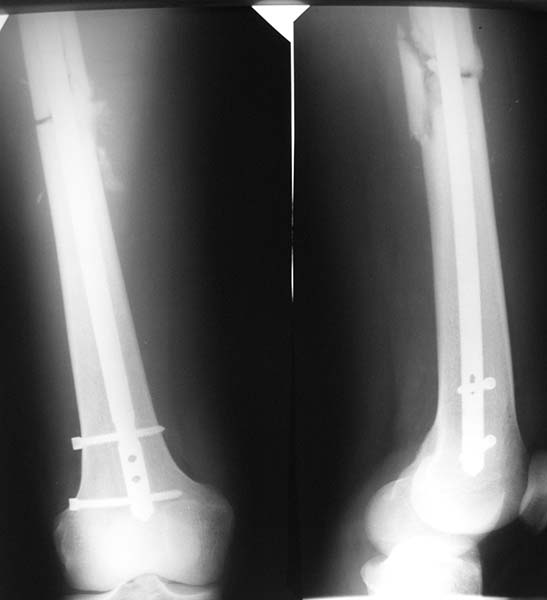

Хотели установить максимально толстый штифт и блокировать динамически.

Послеоперационные снимки прилагаются.